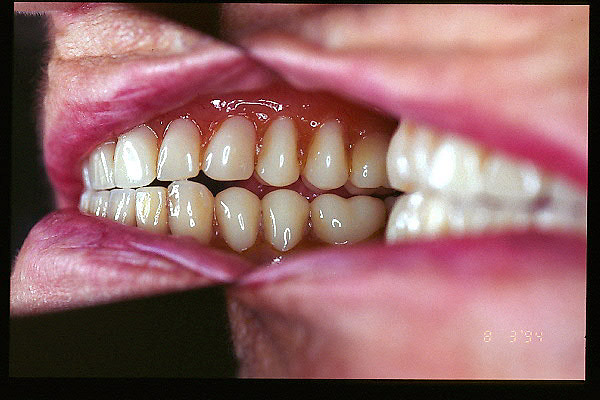

CM Falta de contactos interoclusales